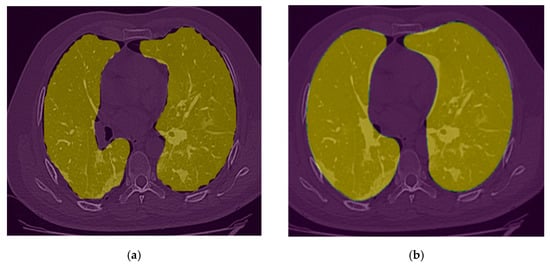

2.3.1. Lung Segmentation